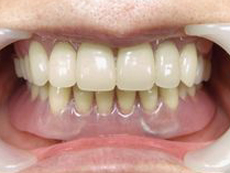

| マグネット式審美入れ歯 愛媛県西条市 60歳 女性 |

もうぼろぼろです。どこで噛んでいるのかわかりません。とても気の毒です。

治療計画

1.上下噛んでいる歯を残して抜歯即左上5番に埋入

2.上の前歯のみ暫間義歯

3.下顎3・3に埋入

4.さらに1ヶ月後、抜歯即上下にマグネット用義歯を装着します。 |